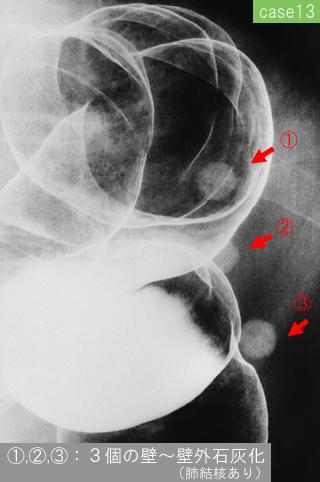

Various benign submucosal tumors and submucosal-tumor like lesions.

[Image-ID:12069]

parte(separada por órganos)

colon/descendente

método de exámen

Rayos X

diámetro mayor del tumor

10 - 14